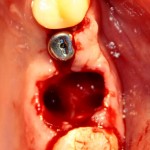

Немедленная имплантация — оптимальное решение в любой клинической ситуации